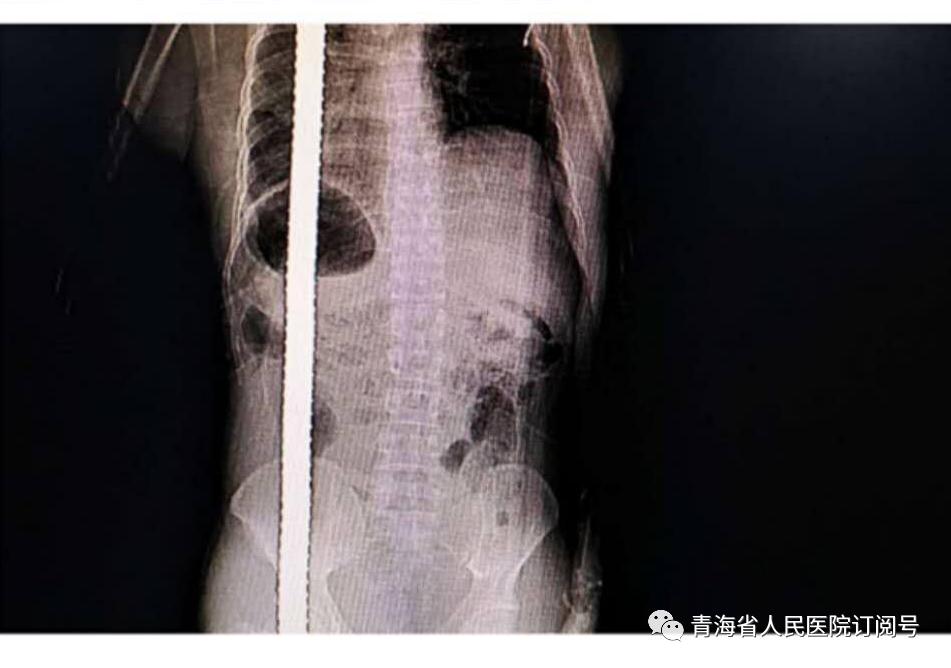

這一刻,所有在崗的醫(yī)護人員立即投入到這場生死大營救中——快速成立搶救小組、快速組織多學科專家團隊會診:CT顯示棍狀金屬異物自左側臀部軟組織穿入,向上貫穿胸腔后自左側頸后部軟組織穿出體外,左側多發(fā)肋骨骨折,血氣胸。盡管患者入院時意識清醒,但鋼筋穿插在身體的長度達88厘米,覆蓋范圍大,涉及多個臟器及部位,情況十分危急。